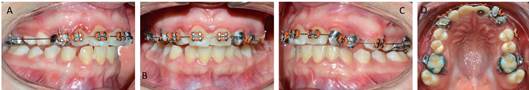

La planificación del tratamiento de Ortodoncia comprendió un tratamiento bimaxilar de compromiso con exodoncias de los dientes 1.3 - 6.3 y 8.3. El plan de tratamiento inicial comenzó con el uso de aparatología Multibrackets MBT .022 con bandas en molares superiores e inferiores. La paciente no consentía sesiones de más de 15 minutos, realizando la instalación parcial superior, a modo de adaptación al tratamiento de ortodoncia, para posteriormente continuar con instalación de arcada inferior. Se derivó a Odontopediatría para las exodoncias de los dientes 1.3 - 6.3 y 8.3. Luego de cuatro meses, la cuidadora refiere que la paciente descementaba intencionalmente los brackets con un lápiz. Si bien se realizó la reposición de éstos, el mal hábito persistió, por lo que se adoptó como alternativa de tratamiento instalar botones, con el objetivo de generar cupla y desrotar los incisivos superiores, continuando con la etapa de alineación y nivelación (figura 4). El mal comportamiento de la paciente persistió en el tiempo, pero aun cuando tenía indicación de retiro de los aparatos, debido a su conducta y la permanente gingivitis, se determinó modificar los objetivos terapéuticos propuestos en un inicio del tratamiento, dando prioridad a lograr el cierre del espacio provocado por la exodoncia del diente 6.3 para la alineación de la arcada superior. Por ellos, se suspendió la instalación de brackets en la arcada inferior y se decidió confeccionar bandas individuales para los dientes que requerían mayor alineación, utilizando como secuencia de arco un Niti Natural .014 y .020, junto con un SS .020 (Figura 5)

Una vez conseguida la alineación y nivelación del arco superior, se cerraron los espacios mediante cadena elastomérica. Al alcanzar el cierre del espacio superior, se realizó el retiro de los aparatos superiores, permaneciendo un pequeño diastema entre los dientes 4.2 y 4.3. La fase activa del tratamiento de ortodoncia duró 22 meses. Como contención se empleó una placa Hawley simple (Figura 6). Al control a los seis meses posterior al retiro de los aparatos, se observan pequeños diastemas en la zona entre los dientes 2.2 y 2.3, junto con las rotaciones de los premolares 1.4 y 1.5 (Figura 7). La paciente no permitió el retiro del botón palatino del diente 2.3, el que debió ser desgastado con instrumental rotatorio. A pesar de los desafíos que fueron presentándose durante el tratamiento, se advierte una mejoría en la alineación dentaria ligado a una oclusión estable.